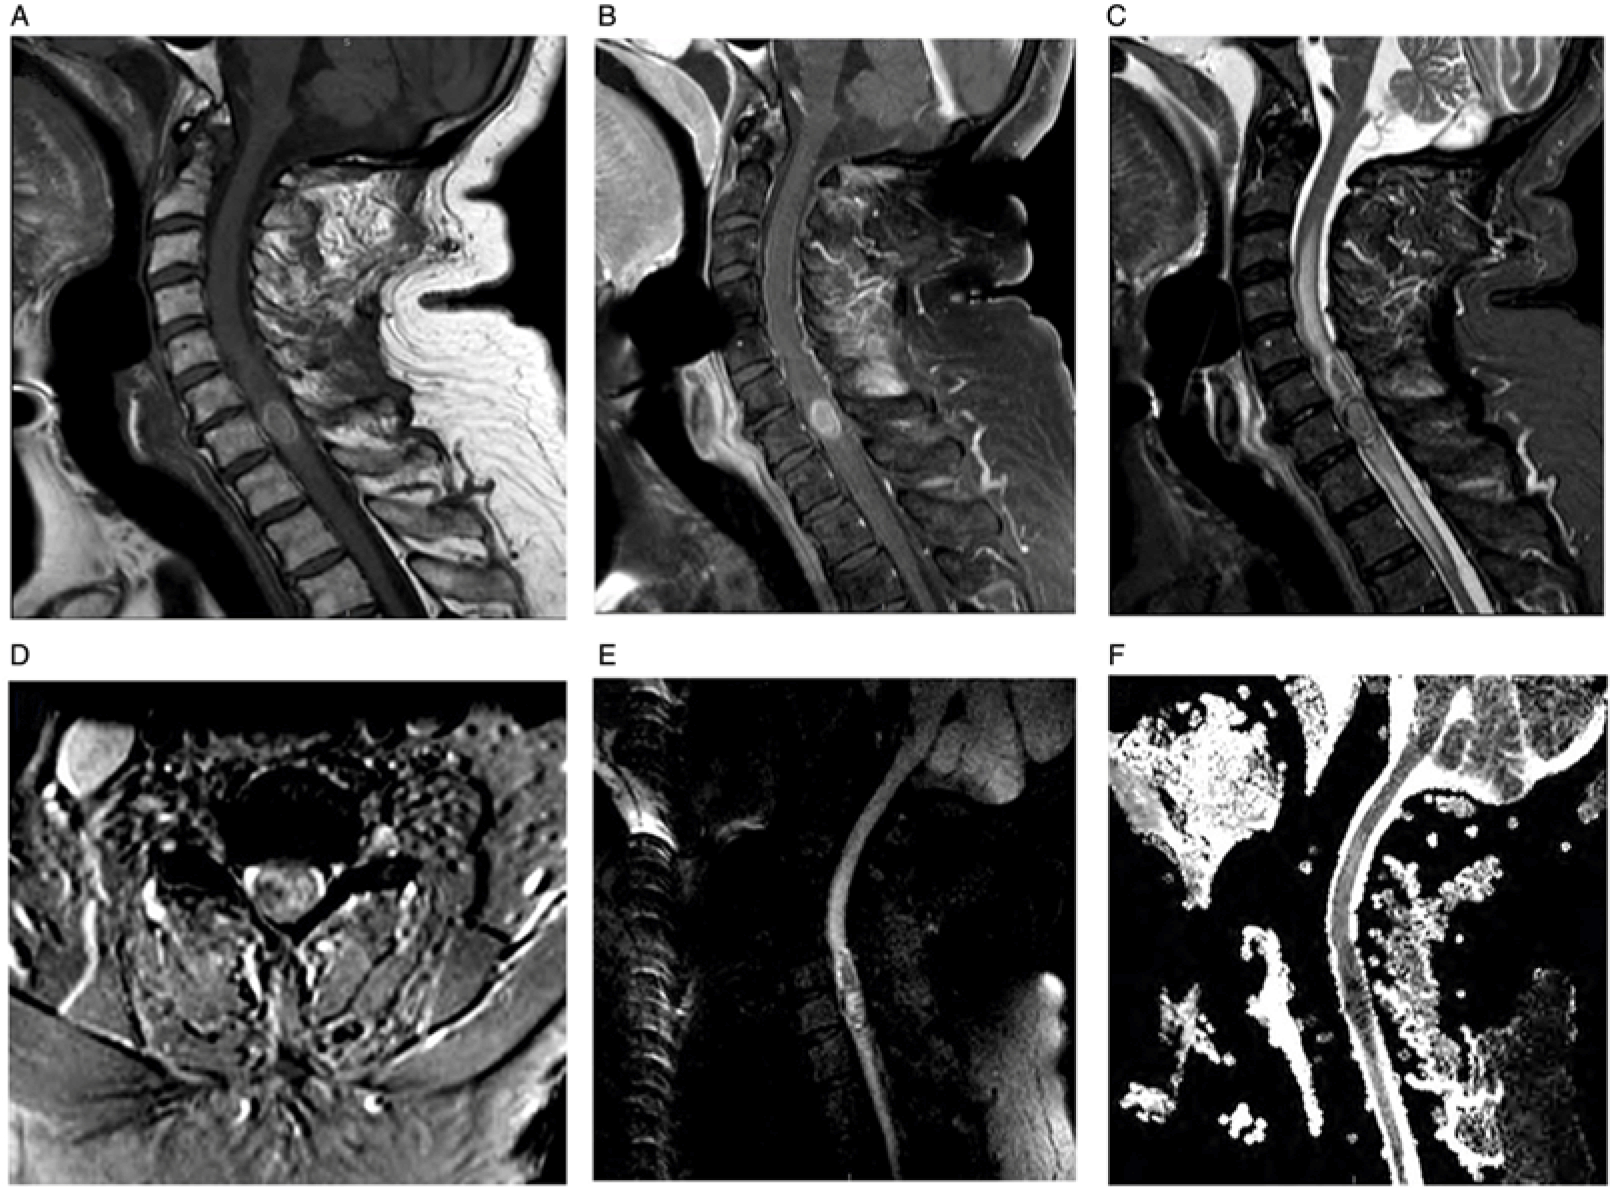

Neuroimaging showed a contrast-enhancing C7 intramedullary lesion with associated hemorrhage and surrounding edema (Figure 1). Preliminary differential diagnoses included metastatic versus primary spinal cord melanoma, melanocytoma, intermediate-grade melanocytic tumor, melanotic schwannoma, and common intramedullary tumors such as ependymoma and astrocytoma. The patient underwent an intradural tumor resection via C6–T1 laminectomy. Intraoperatively, the lesion was soft and black with an intratumoral hematoma. Histologic examination revealed diffuse proliferation of poorly nested epithelioid cells with severe anisonucleosis, prominent nucleoli, and occasional mitoses (Figure 2). Additional work-up with whole-body positron emission tomography/computed tomography (PET/CT), skin/ocular examinations, and upper/lower GI endoscopies were unremarkable, leading to diagnosis of primary spinal cord melanoma. He did not receive adjuvant radiation or systemic therapy. At 18-month follow-up, he has remained without any clinical evidence of disease.

Figure 1: Spine MRI. Sagittal T1 (A), post-contrast sagittal T1 (B), sagittal T2 (C), and axial T2-FFE (D) show an enhancing intramedullary lesion located at the C7 level associated with cord hemorrhage and surrounding non-enhancing signal changes extending from C3 to T3. Sagittal DWI (E) and sagittal ADC (F) reveal intralesional diffusion restriction suggestive of hypercellularity.